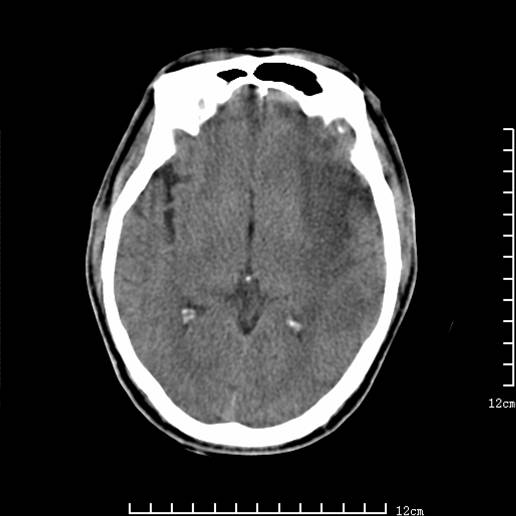

以下图像分别是3月25日凌晨及下午图像、3月27日、4月16日的ct图像。

3月25日下午

1)左侧额颞顶叶、岛叶及基底节区(相当于左侧大脑中动脉供血区)大面积脑梗塞。2)右侧基底节区腔隙性脑梗塞。